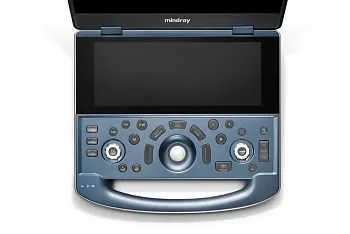

Панель управления

Переход в режим TDI

Переход в режим CW

Вход в M-режим

Вход в режим импульсно-волнового допплера

Вход/выход из режима специальных измерений

Кнопка «Обновить»

Вход/выход из режима общих измерений

Вход в цветной режим

Вход в B-режим

Вход в режим энергетического допплера

Кнопка режима отображения с разделением на два окна

Масштабирование изображения

Ручка усиления и «iTouch»

Кнопка регулировки глубины

Кнопка сохранения статического изображения

Стоп-кадр

Подтверждение операции

Перемещение курсора

Подтверждение операции

Индикаторы

Кнопка «Очистить»

Отображение/скрытие курсора

Многофункциональная ручка

Пользовательские клавиши

Пользовательские клавиши

Пользовательские клавиши

Сенсорная панель управления

Кнопка «Информация о пациенте»

Кнопка переключения между датчиками и режимами исследования

Кнопка сканирования

Кнопка системы управления данными пациента

Кнопка просмотра изображения

Кнопка «Отчет»

Блокировка системы на 10 секунд

Включение или выключение режима настройки

Кнопка завершения исследования